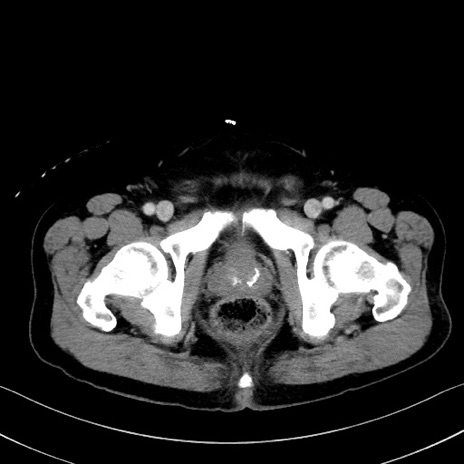

症例35(横断像)

【症例】70歳代 男性

【主訴】腹部膨満、嘔吐

【現病歴】昨日より腹部膨満感出現。本日増悪し、仙痛出現。嘔吐あり、受診。

【既往歴】糖尿病、胆摘後

【身体所見】BP 149/80mmHg、HR 74/min、BT 35.9℃、腹部:膨満、軟、圧痛なし。腸雑音減弱あり。上腹部正中切開瘢痕あり。

【データ】WBC 13500、CRP 1.72